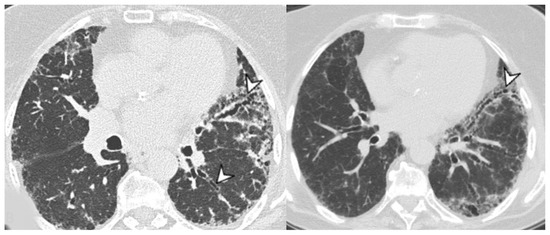

- Chronic progressive fibrosing ILD (reticulation and honeycombing with minimal GGOs on HRCT scans, related to fibrotic NSIP or UIP) [43];

| Lesions | GGO, reticulations, consolidations | consolidations, GGOs | |

| Distribution | Homogeneous; lower lung lobes, along bronchovascular bundles and lung periphery; loss of volume of lower lobes | Patchy; peripheral lower lobes or along the bronchovascular bundles | |

| CT pattern | NSIP OP NSIP-OP UIP DAD-unclassifiable | 50% 20% 25% 10% +/− | 20% 50% 25% <5% ++ |